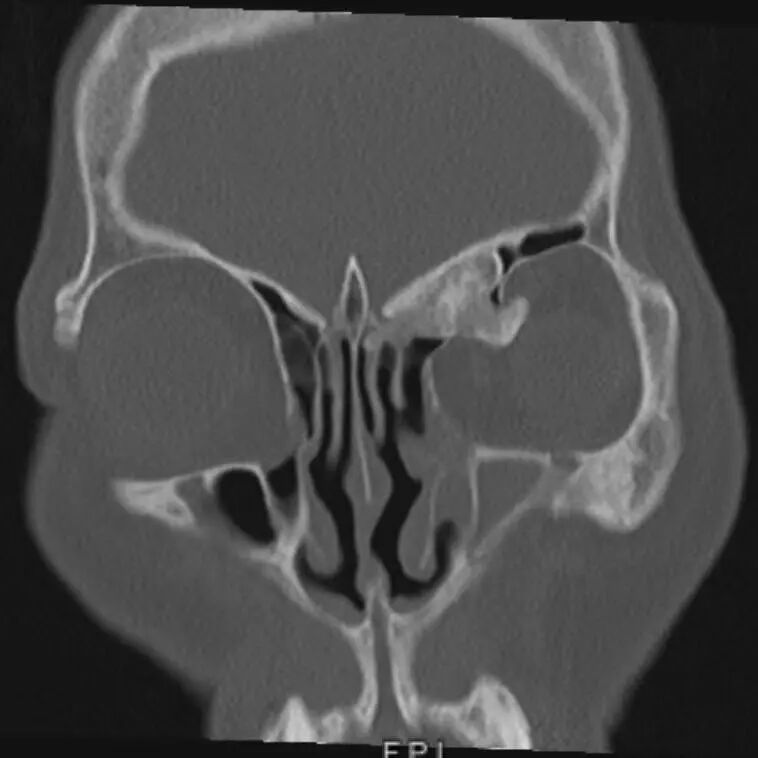

术前CT影像

患者最终来到我院耳鼻咽喉头颈外科寻求转机,经过更为精细的检查,发现这并非简单的眼眶肿物,而是起源于鼻窦、突入眼眶并与颅底紧密连接的一个横跨鼻、眼、颅底三个关键区域的“跨界”骨性肿瘤,稍有不慎,就可能造成颅底损伤,导致脑脊液鼻漏,手术难度与风险陡然升级。